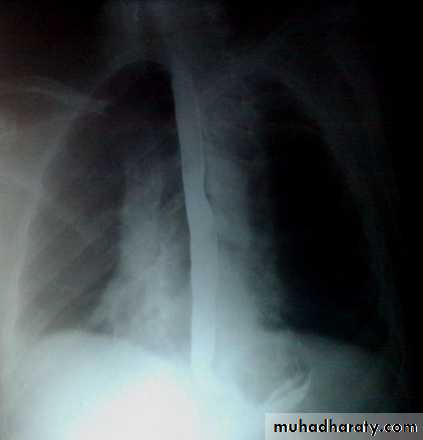

Barium swallow findings:

Tapered narrowing of the lower esophagus, esophageal body is dilated, aperistaltic and food-filled.Clinical features:

Chest X-ray: widening of the mediastinum, aspiration pneumonia.A barium swallow: tapered narrowing of the lower esophagus, esophageal body is dilated, aperistaltic and food-filled.